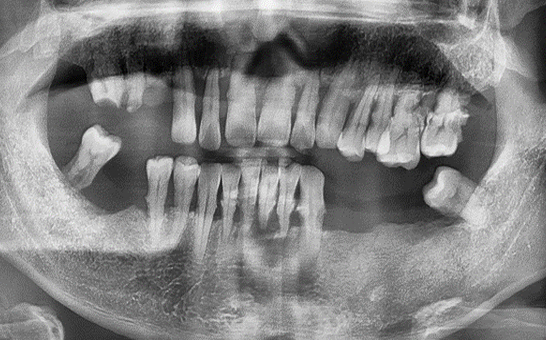

CASE 01 김** / 60대

전악임플란트

치료 시작 전 촬영 2024.01.24 | 치료 완료 후 촬영 2024.12.26

1 예후불량 치아 발치

2 발치 후 즉시 임플란트 식립 및 뼈이식

3 고정성 보철물로 수복 후 일상 회복